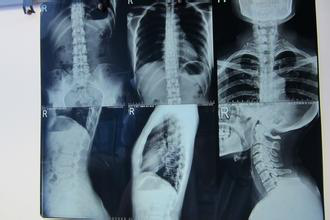

幼年强直性脊柱炎怎样诊断及最佳治疗路径选择

⑹由于儿童骶髂关节的影像学表现在正常情况下即为增宽和不规则,且模糊不清,故X线平片、骨扫描、CT和MRI对于早期诊断很少有帮助。

(2)骶髂关节正位 X线平片发现有单侧或双侧骶髂关节炎,即骶髂关节的关节面模糊,关节间隙变窄或变宽、骨质破坏或骨密度增高,晚期可以出现关节间隙消失;